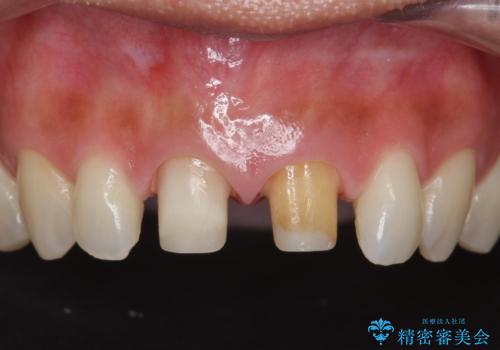

- 3週間後に迫った結婚式までになんとか前歯をきれいにしたいという希望で来院されました。

一回の治療時間を長く取り、限られた時間で最大限の結果を出せるよう集中治療を計画します。

ただ見えるクラウンを白くきれいにするのではなく、長期的な歯の予後を考えると根管治療・ファイバーコア築盛・精密な歯牙形成等クリアすべき条件は多々あると言えます。